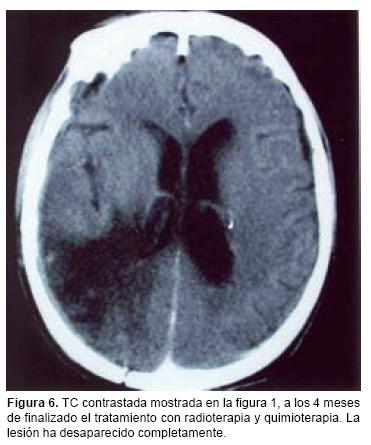

El período de seguimiento fue de 3 a 72 meses, tiempo en el que, además de la valoración clínica con visitas hospitalarias cada mes y medio, se efectuaron estudios de imagen como control, en especial resonancia magnética de encéfalo simple y con medio de contraste cada tres meses, como parte del protocolo, a fin de detectar la posible recurrencia tumoral, y en especial cambios sugestivos de radionecrosis.

La supervivencia promedio en 12 pacientes tratados únicamente con radioterapia fue de 11 meses, la que se incrementó a 36 meses en los 10 pacientes restantes que recibieron además tratamiento con metotrexato. En la mayoría de los pacientes sometidos al tratamiento combinado (radio y quimioterapia) se notó franca mejoría no sólo en el cuadro clínico, sino también en los estudios de imagen realizados durante el seguimiento, apreciándose incluso, la desaparición de la lesión o lesiones (Figura 6). Todos los pacientes que recibieron quimioterapia presentaron alteraciones en las pruebas de funcionamiento hepático, sin llegar al daño hepático agudo; además, dos de ellos mostraron datos de insuficiencia renal aguda con duración de 10 días en promedio. En un caso se presentó un cuadro de gastritis aguda requiriendo de su hospitalización y tratamiento intravenoso con inhibidores de bomba de protones. Los pacientes que recibieron el tratamiento combinado presentaron astenia y adinamia intensa mientras se aplicó el tratamiento.